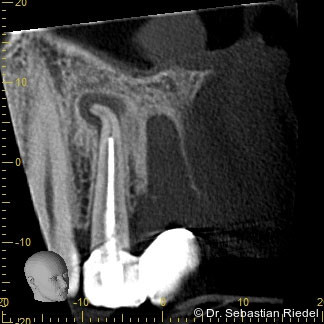

Für eine effiziente Desinfektion bis zum Apex strebe ich eine Aufbereitungsgröße in der Dimension 35/06 an. Bei sehr schlanken Wurzeln oder bei Wurzeln mit sehr starken Krümmungen endet die Aufbereitung bei 35/04, um die mögliche Gefahr von Feilenfrakturen weiter zu reduzieren.

Die von mir verwendeten modernen Feilensysteme zeigen, dass bei korrekter Indikationsstellung eine effi­zien­te und sichere Wurzelkanalaufbereitung möglich wird, welche die Grundlage für eine optimale Desinfektion und Obturation der Kanalsysteme darstellt.